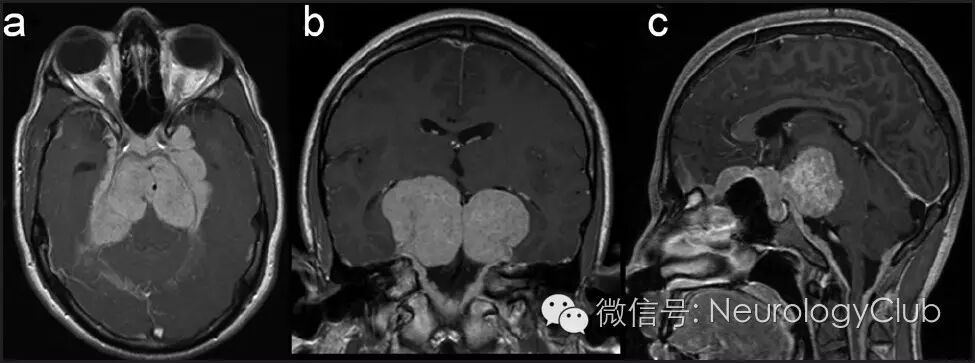

(图4:治疗后6月的增强MRI。可见肉芽肿性病变明显缩小,颈部硬脊膜恢复正常)

上颌窦病灶内镜活检提示非干酪样肉芽肿伴慢性炎性细胞浸润和浆细胞(图3)。患者血管紧张素转换酶升高(61.44U/l),高钙血症,结合组织病理学表现,诊断为神经结节病。免疫治疗6月,复查头颅MRI提示肉芽肿显著缩小(图4)伴T2明显低信号(图5)。临床上,患者步态和听力改善,目前生活可自理。